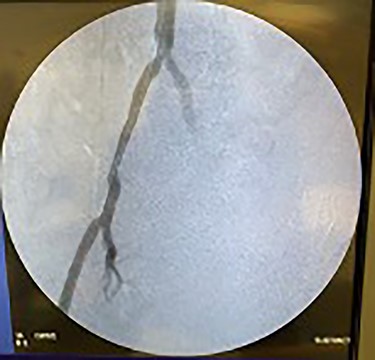

Catheter arteriogram results showed significant occlusion of the left iliac artery (Figs 3 and 4), the right iliac artery (Fig. 1), as well as the distal abdominal aorta (Fig. 2). There were numerous collateral vessels noted, indicating the presence of long-standing proximal stenosis (Fig. 1). The decision was made to use angioplasty to help widen the areas of stenosis. An 8 mm × 40 mm Passeo balloon was advanced from the right femoral artery into the left iliac artery (Fig. 7) and insufflated to 6 mmHg (Fig. 6). The balloon was allowed to remain expanded for 1 min and then was deflated. Next, the distal aorta was repaired in a similar fashion. The balloon was advanced into the distal aorta from the right femoral access and insufflated to 12 mmHg (Fig. 8). The balloon was allowed to remain expanded for 90 s.

Fluoroscopy of bilateral iliac arteries showing significant arterial disease.